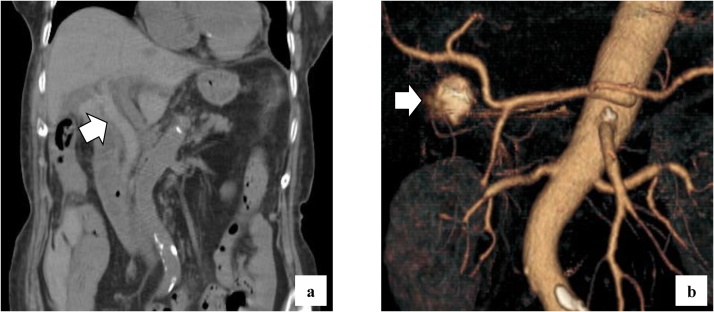

She complained of back pain and right hypogastric pain on postoperative day (POD) 12. Blood examination revealed anemia and elevated levels of serum bilirubin and hepatobiliary enzymes. The total bilirubin (T-bil) level was 2.73 mg/dL (normal range: 0.2–1.2 mg/dL), direct-bilirubin (D-bil) level was 2.36 mg/dL (normal range: 0–0.4 mg/dL), aspartate aminotransferase (AST) level was 243 U/L (normal range: 10–40 U/), alanine aminotransferase (ALT) level was 82 U/L (normal range: 5–40 U/L), alkaline phosphatase (ALP) level was 2018 U/L (normal range: 100–340 U/L), and hemoglobin (Hb) level was 6.5 g/dL (normal range: 12–15 g/dL). Computed tomography (CT) revealed a high absorption area in the common bile duct (CBD), and hemobilia was suspected (Fig. 1a). Contrast-enhanced CT revealed no active bleeding into the abdominal cavity, but a pseudoaneurysm was observed in the cystic artery (Fig. 1b). Endoscopic retrograde cholangiopancreatography (ERCP) revealed contrast deficiency in the CBD, although there was no leakage of contrast outside the CBD (Fig. 2a). An ENBD tube was inserted on POD 12 (Fig. 2b) and an ERBD stent was placed in the CBD on POD 13. The fluid drained from the ENBD tube was a mixture of blood, bile, and pus, and was suggestive of a superimposed bacterial infection. A diagnosis of hemobilia was made as the fluid drained from the ENBD was blood. The patient also presented with melena. Therefore, conservative treatments, such as blood transfusion and administration of antibiotics, were commenced. Due to gradual deterioration of renal function (eGFR reduced to 7 mL/min/1.73 m2) and reduction in urine output during the treatment, hemodialysis was temporarily introduced on POD 15. After controlling hemobilia and biliary infection, renal function improved (eGFR increased to 23 mL/min/1.73 m2) and hemodialysis was discontinued on POD 30. Blood-based investigations revealed that the levels of hepatobiliary enzymes were improving gradually, while contrast examination using the ENBD tube showed no leakage of the contrast medium outside the CBD on POD 27 (Fig. 2c). The ENBD tube was removed on POD 27, the ERBD stent was removed on POD 54, and she was discharged on POD 66.